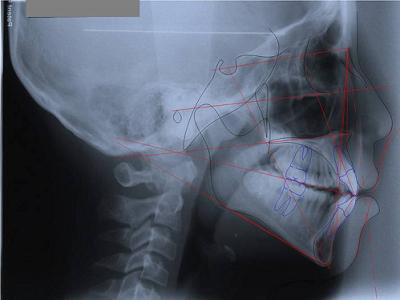

Вначале проводится первичный осмотр и диагностика пациента. Для того чтобы определить степень проблемы, нужно сделать панорамный снимок челюсти и только после этого делать выводы о состоянии зубов. На этом этапе врач предварительно может просчитать длительность, а также общую стоимость предстоящего лечения. Непосредственно после этого начинается лечение. Если же при осмотре выявлен кариес, ротовая полость санируется, а зубы обязательно покрываются слоем фтора. Во время ортодонтического лечения пациентам одевается специальный аппарат, который может быть съемным или стационарным. Съемный выглядит как пластмассовая пластинка, имеющая профилактический или лечебный характер. Такие пластины изготавливаются индивидуально для каждого пациента, учитывая особенности зубного ряда. Каждая пластина выполнена таким образом, что во время ношения постепенно происходит исправление неправильного прикуса. Обычно съемные пластинки назначают детям 6-12-летнего возраста. Как раз в этот период зубной ряд не сформировался полностью и легко поддается коррекции. Такие же пластины могут назначать и взрослым.